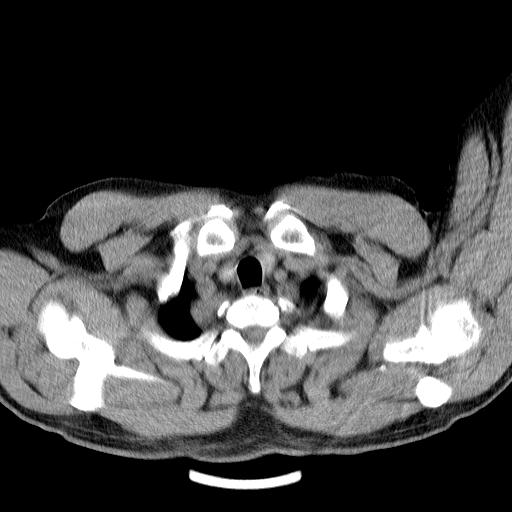

男,51岁,体检时发现右上纵隔高密度影。

右上纵隔脊柱旁圆形结节,密度均匀,边界清楚——考虑神经源性肿瘤!